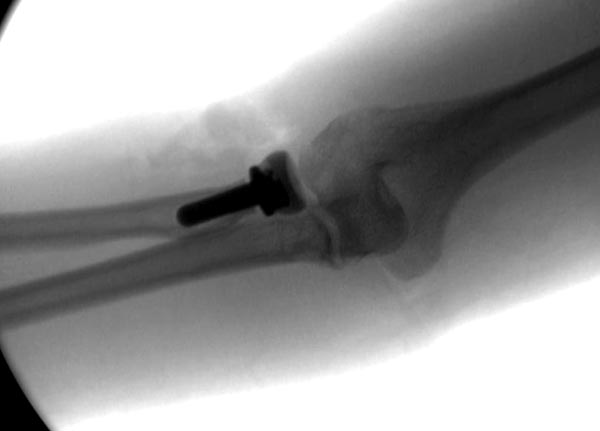

Имя     : 1 Elbow radial head fx.jpg

Тип     : image/jpeg